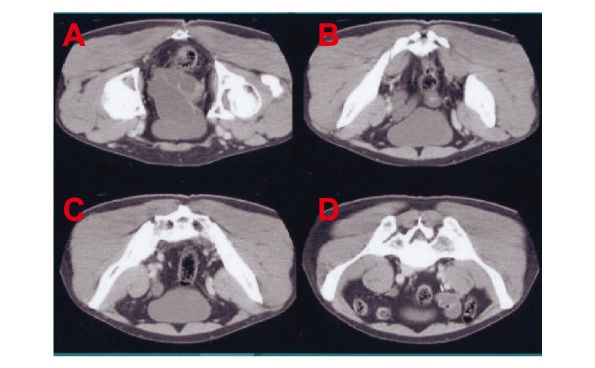

図Eは「骨盤補正二段ベルトの装着による恥骨結合難解」の様子を光学解像X線解析により最長1年間で経時的に計測した様子です(被験者は28歳女性 A:装着前 B:装着後3ヶ月 C:装着後6ヶ月 D:装着後1年)。

その結果、脊髄根元付近(上方からみて左右)にのみ集中していたhGHが「骨盤補正二段ベルト」の装着によって分散を始め、最終的には「恥骨結合軟骨」を包含するように均一に分散(ラッピング修復)されました。

下の図4は、同じ被験者(図E参照)のX線撮影結果(レントゲン)です。「骨盤補正二段ベルト」の装着により、その95日後には軟骨部位の解離間隔の修復されている事が分かります。